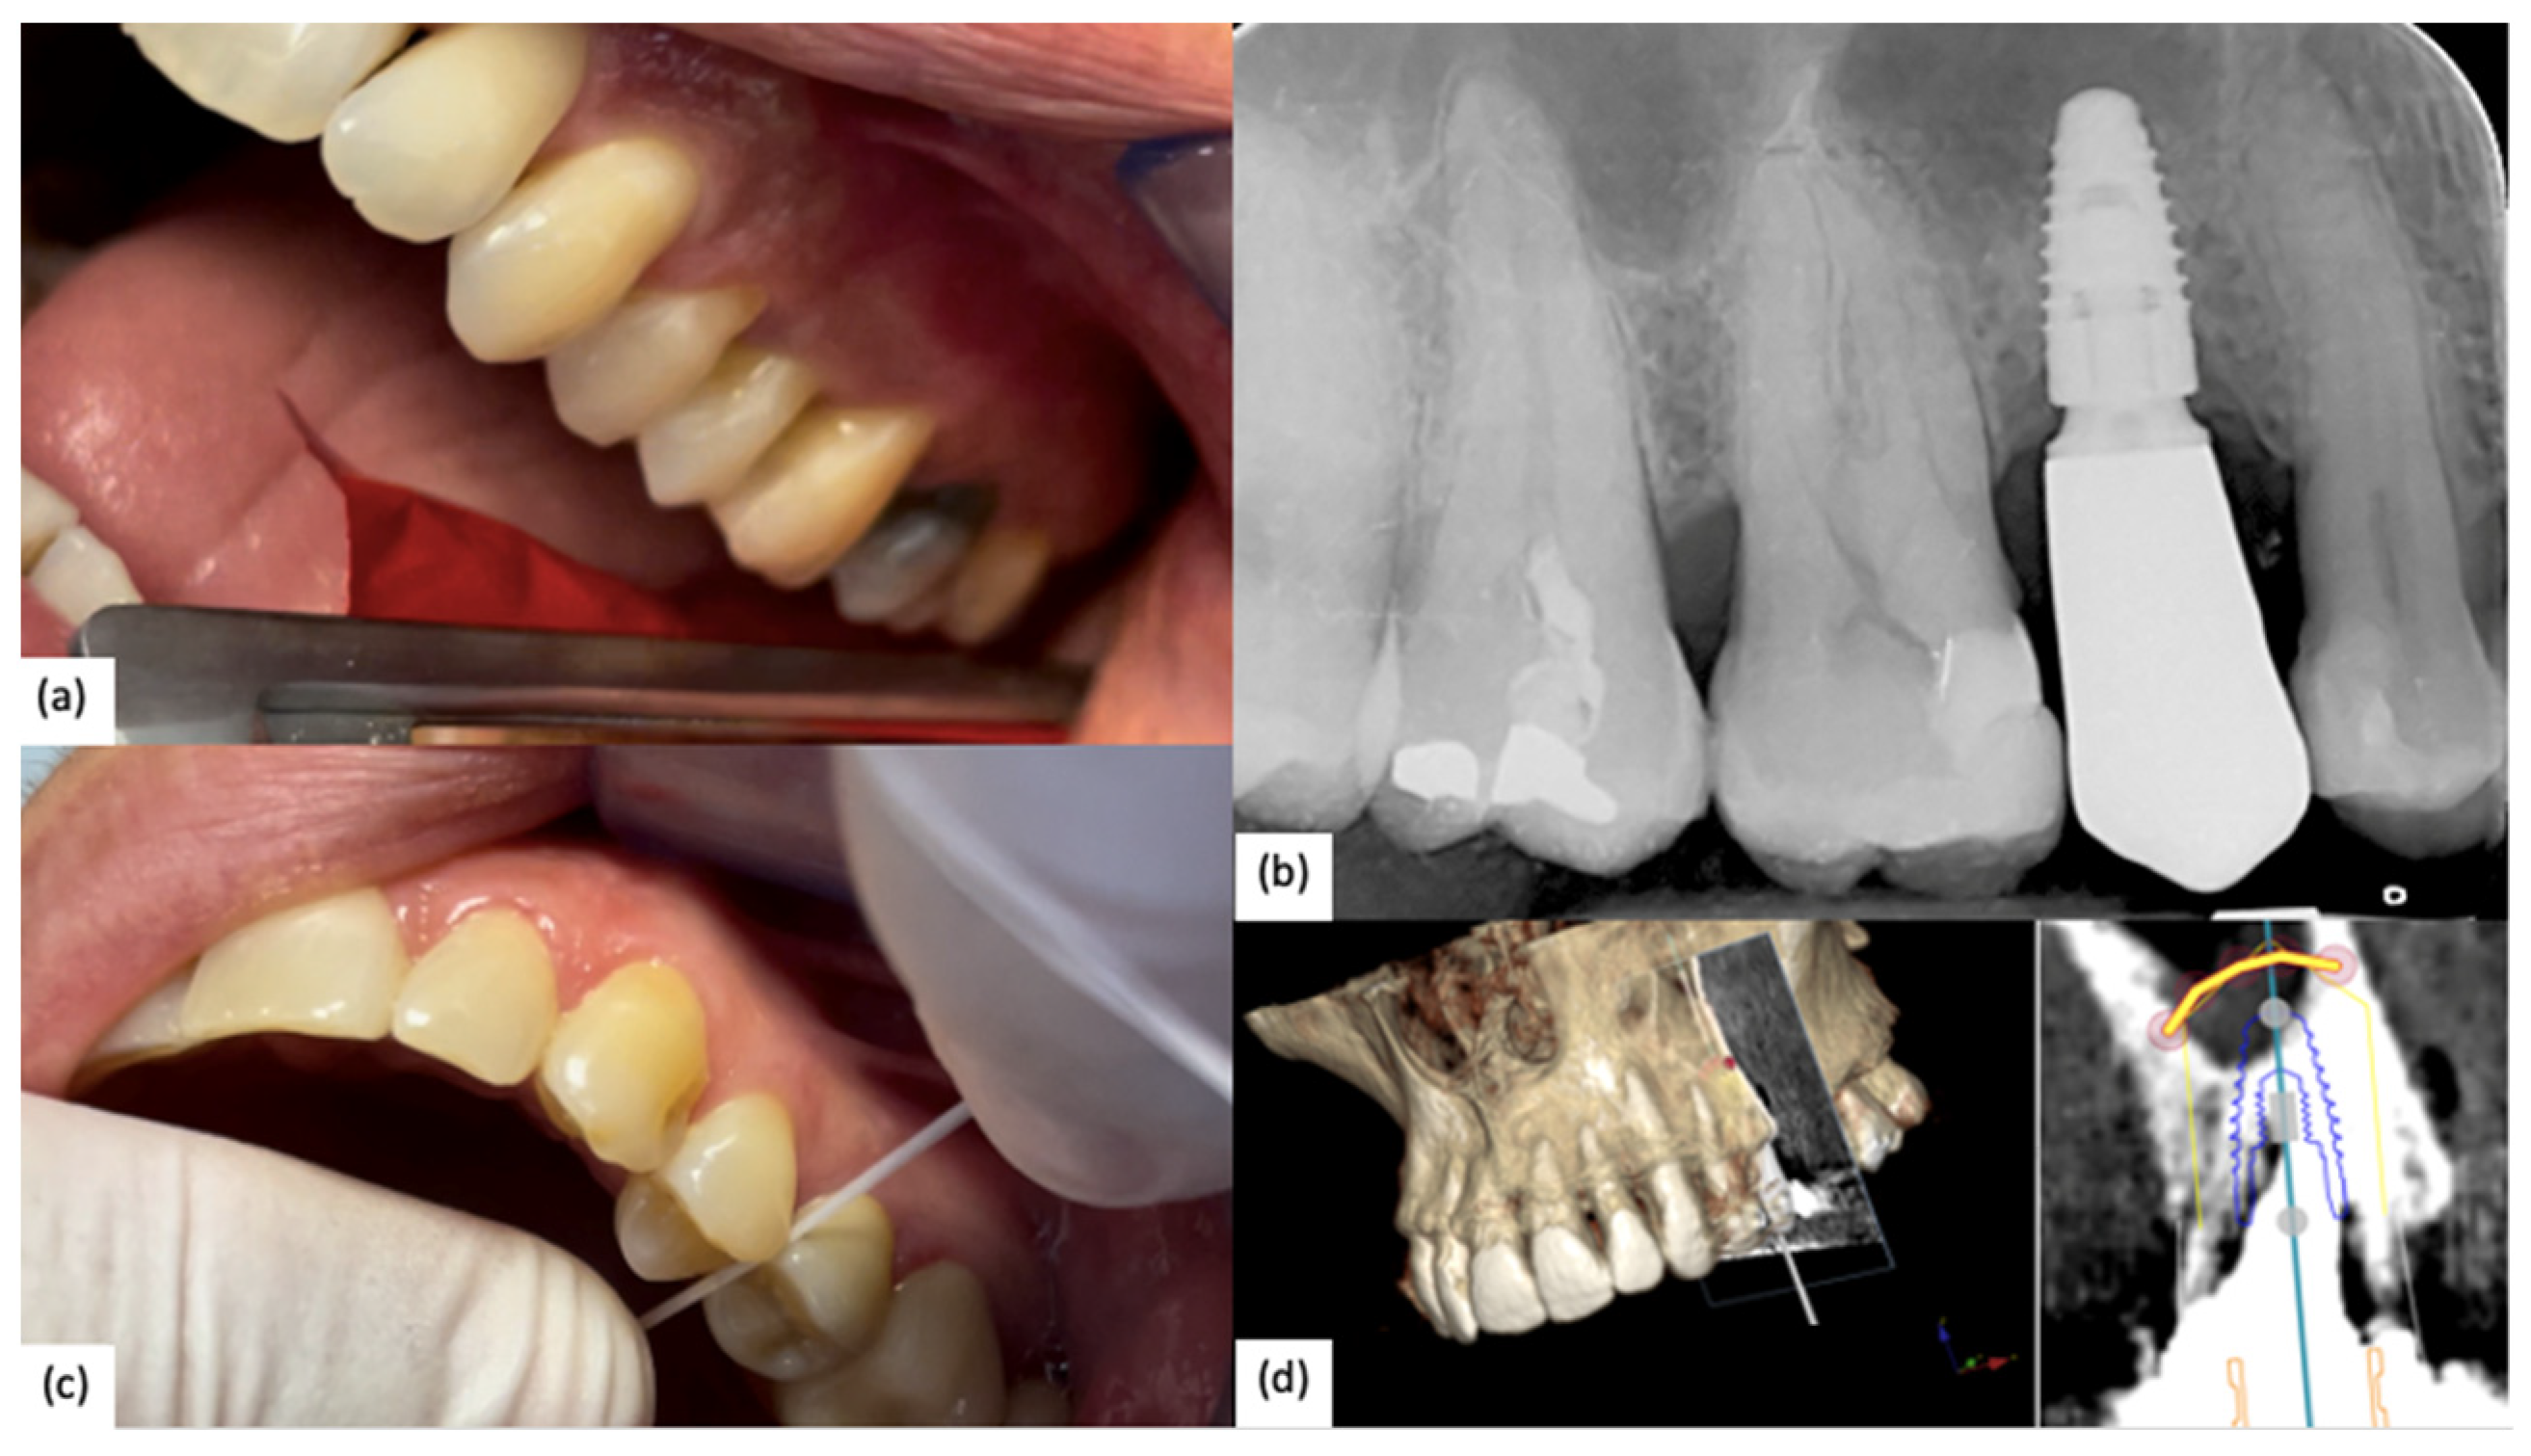

The intraoral Rx of three patients are reported in Figure 4.

Figure 4. Intraoral Rx: (a) 2.1 after 1 year which followed the fully digital workflow after a GBR (Nobel Biocare N1); (b) 2.5 and 2.4 after conventional workflow that shows an implant–abutment misfit of 2.4 that needs to be corrected (Nobel Parallel TiUltra CC); (c) 1-year follow-up Rx of 2.7 and 2.6 which followed a combined analog–digital workflow (Nobel Active TiUltra CC).